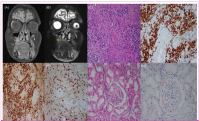

A 68-year-old female patient, whom provided informed consent, experienced progressive weakness, fatigue, weight loss, dyspnea, and cough over 2 years. During this period, she was treated several times for pneumonia but experienced recurrent elevations of acute-phase reactants (APRs) despite the use of antibiotics. She presented to the dental clinic with gingival swelling and pain. Radiological and clinical examination revealed a mass measuring approximately 3 cm extending from the base of the maxillary sinus to the oral cavity (Figure 1A and B). The biopsy, initially suspected of malignancy, revealed markedly high levels of plasma cells immunostained for IgG and IgG4, with an IgG4:IgG ratio of 25%-30%, suggesting IgG4-related disease (IgG4-RD) (Figure 1C-F). The patient was referred to our hospital. The rheumatological examination confirmed ongoing constitutional symptoms. Laboratory results showed an erythrocyte sedimentation rate (ESR) of 135 mm/h (0-20), C-reactive protein (CRP) level of 179 mg/L (0-5), complement C4 level of 43 mg/dL (0-40), and complement C3 level of 178 mg/dL (90-180). The IgG and IgG4 levels were 2508 (700-1600) mg/dL and 0.59 (0.03-2) g/L, respectively. Autoantibodies, including rheumatoid factors, anticyclic citrullinated peptide antibodies, antinuclear antibodies, and antineutrophil cytoplasmic antibodies, were negative. The renal function tests and urinary microproteinto-creatinine ratio were within normal limits. Serum protein electrophoresis showed polyclonal hypergammaglobulinemia. Echocardiography and infection screenings were performed to rule out other causes. Malignancy was ruled out by positron emission tomography/computed tomography. Based on the clinical, radiological, and histopathological findings, the patient was diagnosed with IgG4-RD and treated with methylprednisolone (1 mg/kg) and methotrexate (15 mg/week). The APRs decreased rapidly with clinical improvement. In retrospect, the diagnosis was made in accordance with the 2019 ACR (American college of rheumatology)/EULAR (European league against rheumatism) Classification Criteria, based on the presence of a tumefactive lesion in the maxillary sinus on imaging, systemic inflammation with markedly elevated APRs, dense lymphoplasmacytic infiltration on histology, immunostaining results (an IgG4:IgG ratio of 0%-40% and >10 IgG4+ plasma cells per high-power field), consistent clinical findings, a rapid clinical and biochemical response to treatment, and the exclusion of other mimickers.

However, during steroid tapering in the 4th month, proteinuria developed (4.7 g/day), and ESR (120 mm/h) and CRP (124 mg/L) levels increased again. The creatinine level was normal. The methylprednisolone dose was increased to 1 mg/kg, and a renal biopsy was performed, which revealed renal AA amyloidosis (Figure 1G and H). Familial Mediterranean fever was ruled out. The existing findings confirmed the diagnosis of secondary AA amyloidosis owing to IgG4-RD. Rituximab (1 g) was administered on days 1 and 15. Six months after treatment, the CRP (3.78 mg/L), proteinuria (0.2 g/day), and IgG levels (970 mg/dL) were all within the normal ranges.